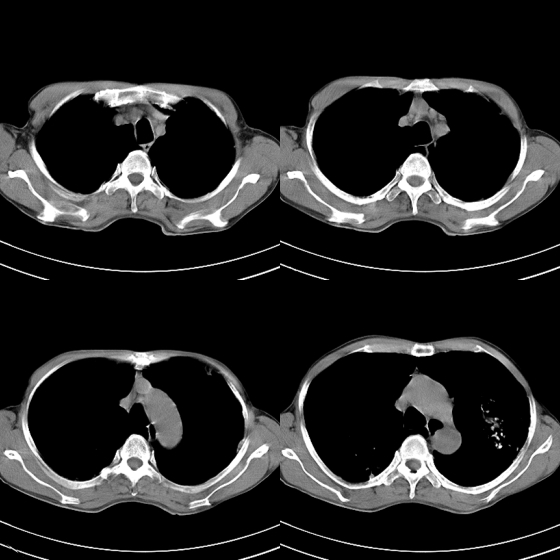

标题: CT21797:M65y,矽肺团块内空洞?

m65y,咳嗽、咯痰,煤工工作史10+年。低热,无明显脓臭痰。临床怀疑tb。

我也明知故犯一次!1、矽肺伴结核, 右下病变不排除瘢痕癌;2、慢支、肺气肿、多发肺大泡并气胸。

双侧矽肺,肺大泡,肺气肿

矽肺伴结核(左肺上叶病灶内空洞形成),右侧气胸,两肺多发性肺大泡。

考虑矽肺伴结核;

右侧气胸,左肺上叶肺大泡

、矽肺伴结核同时合并感染, 右下病变不排除瘢痕癌;2、慢支、肺气肿、多发肺大泡并气胸。